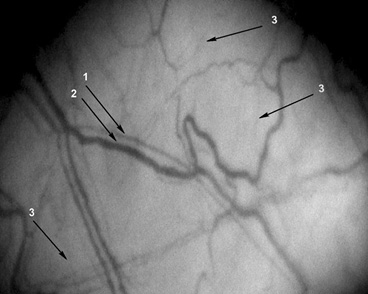

Для иллюстрации материалов на рис. 1–3 представляем фрагменты МЦР бульбарной конъюнктивы некурящего, курящего и прекратившего курить пациентов с АГ.

Рис. 2. Фрагмент микроциркуляторного русла конъюнктивы. Увеличение ×96. Пациент Д. 40 лет, курит 31 год по 20 сигарет в день, продолжает курить. Страдает артериальной гипертензией 3-й степени, риск 3, в течение 15 лет. Артериальное давление на момент исследования 163/101 мм рт.ст., пульс 92 в минуту. 1 — артериола (d=9,3 мкм); 2 — венула (d=26,4 мкм), артериоло-венулярный коэффициент 0,24; 3 — капилляры (d≈6 мкм), количество капилляров на 1 мм2 поверхности конъюнктивы 2,17 ед./мм2